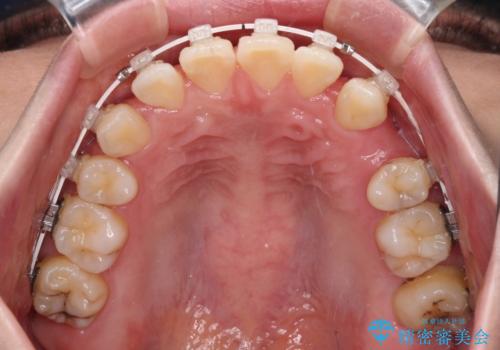

- 前歯のデコボコや口元の突出感、口の閉じにくさを気にして来院された患者様です。

上下左右第一小臼歯4本を抜歯し、ワイヤー装置にてデコボコを解消しながら口元を引っ込めるよう矯正治療を行うこととしました。

抜歯スペースを閉じている過程で、左側の上下犬歯が引っかかってしまい、進捗が停滞しましたが、当初予定の2年~2年半の間で無事に治療を終えることができました。